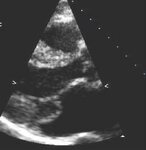

Parasternal long-axis view showing posterior mitral leaflet prolapse

From the collection of Samir Kapadia and Mehdi H. Shishehbor